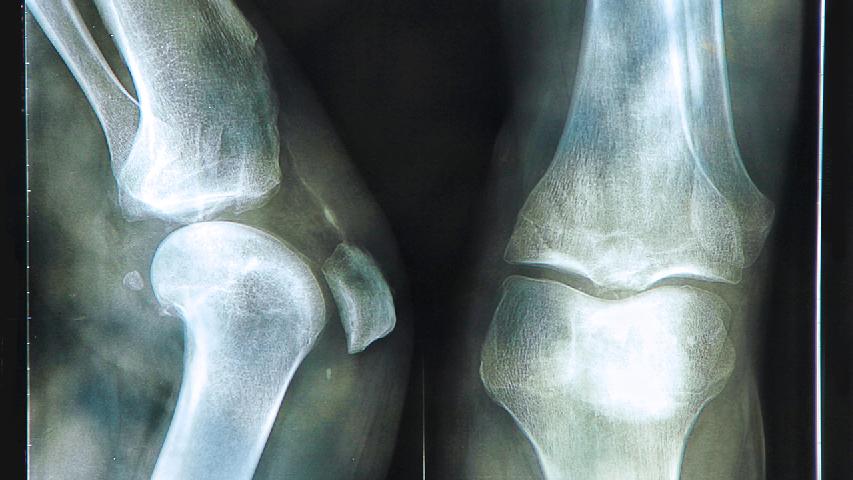

怎么预防骨质疏松